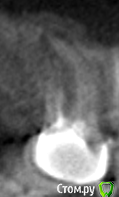

7 зуб с культевой вкладкой. Есть возможность бесплатно перелечить или удалить и поставить имплант (бесплатно). Что выбрать?

Как сказали выше, качество снимков плохое. Подобие культевой вкладки на снимке еле улавливаю, не исключено что можно перелечить. Если говорить об импланте, нужно сделать КТ.